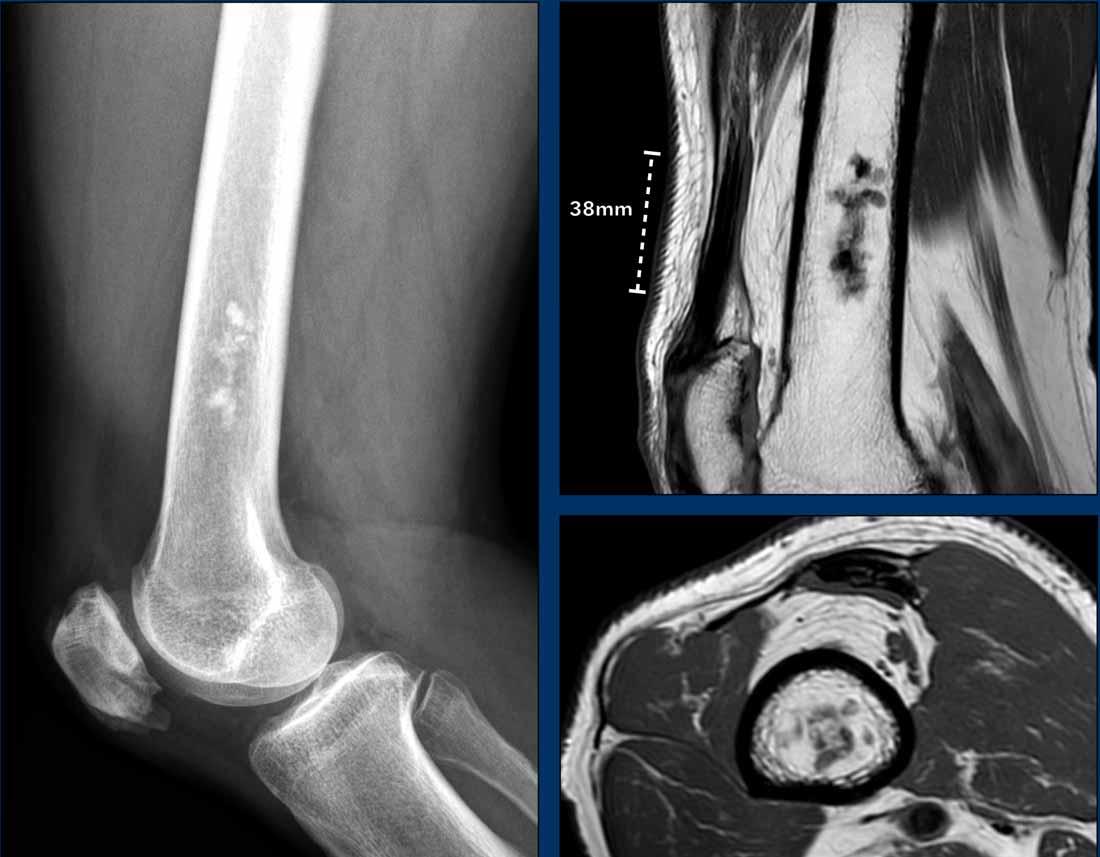

Dedifferentiated chondrosarcoma

Đầu tiên hãy xem các hình ảnh của bệnh nhân 79 tuổi bị u xương.

Sau đó tiếp tục đọc.

Hình ảnh

Phim X-quang cho thấy một khối u lớn ở thân xương đùi với hình ảnh vôi hóa dạng bỏng ngô điển hình ở phần xa và thành phần tiêu xương nhiều hơn ở phần gần.

Hình ảnh phóng đại chi tiết ở tư thế nghiêng cho thấy khối u xâm lấn vỏ xương và nguy cơ cao gãy xương bệnh lý.

Phần đuôi của khối u có hình ảnh giống u sụn không điển hình (ACT) với hiện tượng lõm vỏ xương khu trú, trong khi phần đầu có hình ảnh giống u sụn ác tính độ cao (CS độ cao).

Kết luận

Đây là hình ảnh điển hình của sarcoma sụn phản biệt hóa, với một phần có biểu hiện như khối u sụn độ thấp đến trung bình với sự chuyển tiếp đột ngột sang thành phần sarcoma độ cao (đôi khi không có nguồn gốc sụn).

Phân nhóm này

thường gặp ở người lớn tuổi.

Tỷ lệ sống còn toàn bộ của sarcoma sụn phân hóa kém rất thấp so với sarcoma sụn độ II và độ III, do bệnh nhân thường đã có di căn phổi và xương tại thời điểm chẩn đoán.

Continue with the next images…

Lưu ý khuyết tật vỏ xương trên ảnh T2 DIXON axial và khối mô mềm xung quanh.

Một phần khối u không ngấm thuốc và vùng chất nhầy này cho thấy đây là u sụn ác tính độ cao.

Như trên phim X-quang, trường hợp này là một chondrosarcoma phân hóa kém điển hình, trong đó phần dưới có biểu hiện như một ACT và phần gần như một sarcoma độ cao.

Thường gặp dưới dạng khối u lớn ở bệnh nhân cao tuổi.

Hình ảnh tưới máu cho thấy

sự tăng cường tín hiệu không đồng nhất trong khối u sụn biệt hóa kém này.

Phần nhầy (đường màu xanh lam)

không có sự tăng cường tín hiệu.